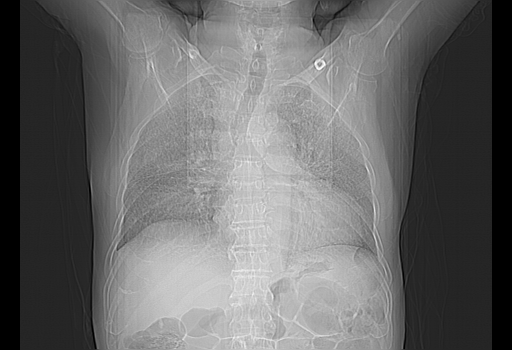

今天复查肺部CT,发现双肺广泛磨玻璃样改变。所以我把3月19日和5月9日相隔50天的肺部CT上传。请大家会诊。

2009年3月19日肺部CT片。

2009年3月19日肺部CT

5月9日肺部CT(在4月27日齐鲁医院肺部CT描述部分肺组织磨玻璃样改变,12天后肺组织广泛磨玻璃样改变)

大致读了系列胸部CT:纵隔窗无明显异常,肺窗:从4、27至今:主要是双肺中下野外带可见毛玻璃样改变,目前处于急性肺泡炎阶段,至于原因考虑1、结替组织或胶原血管性疾病所致?2、恶性疾病如恶组在肺部所致的表现或细支气管肺泡癌?3、药物或其它原因如肺蛋白沉着症所致肺泡炎目前不太可能?总之,明天就去请我院的呼吸科、感染科、血液科和临免专家会诊哈。